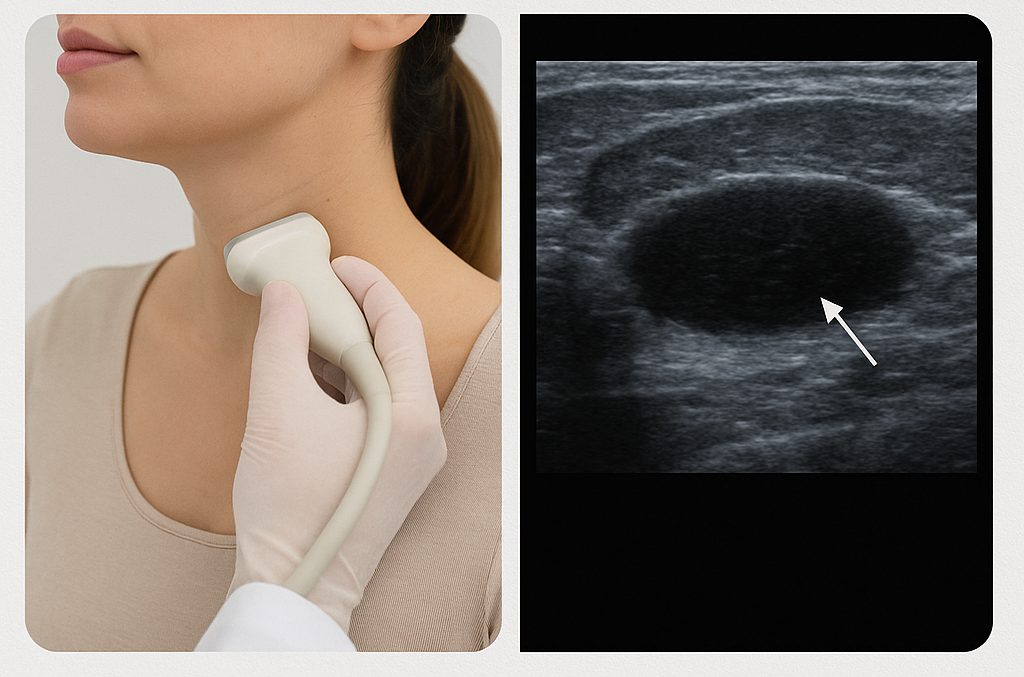

УЗИ лимфатических узлов — важный метод диагностики, который по состоянию данного периферического органа человеческого организма может рассказать о состоянии здоровья пациента. Лимфоузлы группируются в жизненно важных локализациях тела: паховой, подколенной, затылочной, ушной, шейной, челюстной, подмышечной, брюшной, грудной и иных областях. Во время процедуры, врач фиксирует размеры узлов, их локализацию, плотность тканей, поперечное сечение, эхогенность, форму, количество, структуру, питающие их сосуды, наличие аномалий развития или новообразований.